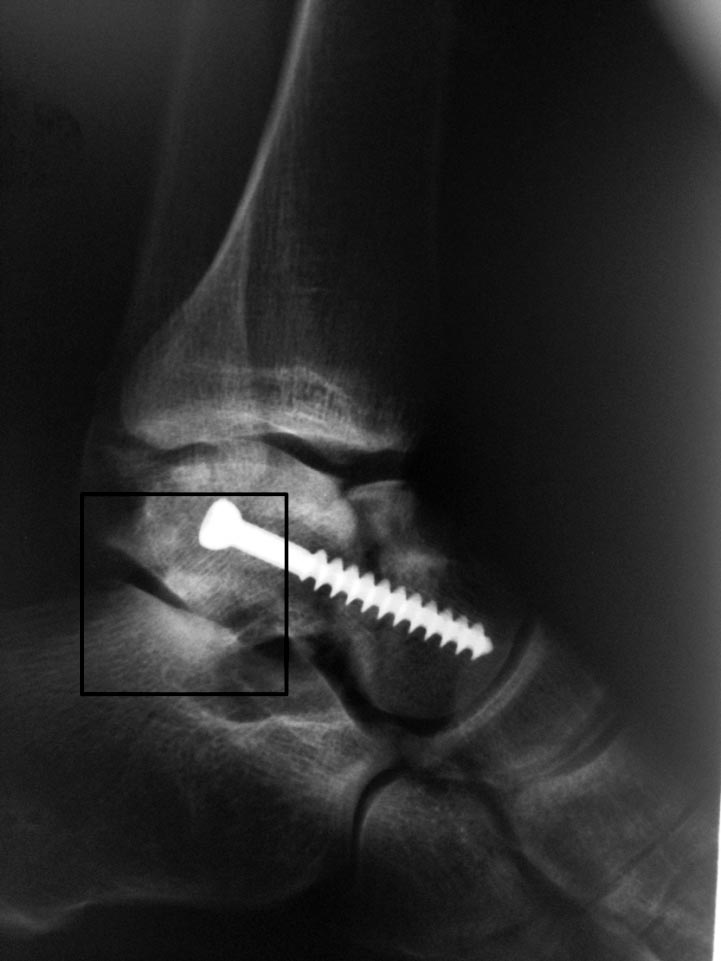

Рентгенограммы после операции

Посмотрите снимки еще раз, пожалуйста . На прямой проекции имеется " ступенька", которая устранена. На боковой проекции до операции имеется диастаз, и винтом дана компрессия. Также удалены осколки из заднего отдела, которые при сращении давали бы проблемы в этом отделе .